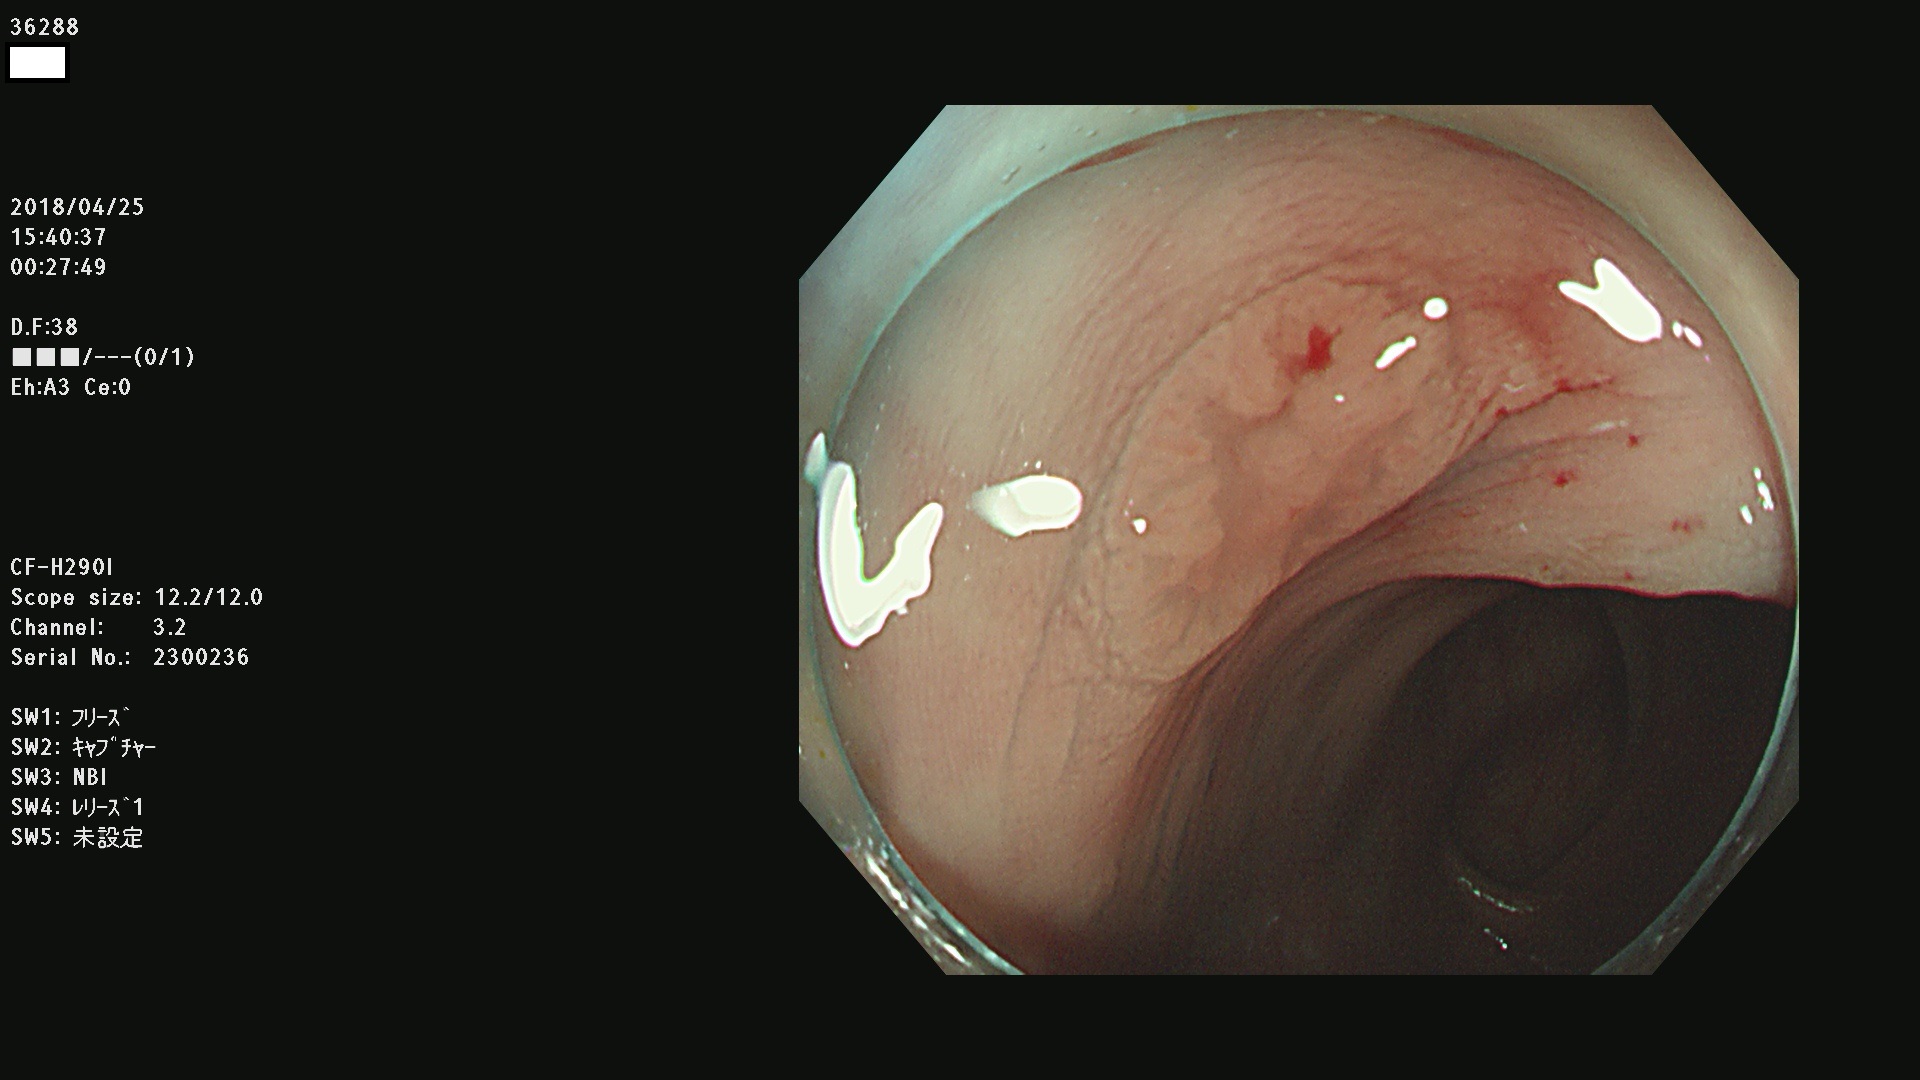

36201 36202 36203 36205 36207 36209 36210 36212 36213 36214 36215 36217 36220 36221 36222 36224 36225 36226 36227 36229 36230 36231 36232 36235 36236 36238 36240 36243 36244 36246 36247(SSAPのみ。SPS) 36248 36249 36251 36252 36253 36254 36255 36256 36257 36258 36259 36261 36262 36264 36265 36267 36269 36270 36272 36274 36275 36276 36279 36280 36281 36283 36285 36288 36289 36291 36292 36295 36296 36297 36299

発見困難で危険性の高い平坦型病変(上記100名より抽出)